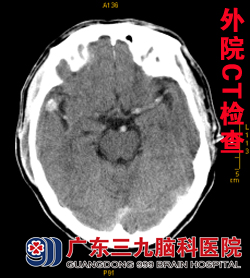

入院查体见罗先生血压196/90mmHg,意识清楚,言语流利,肢体活动灵活。其今年2月的头颅CT检查示:1.多发性腔梗,2.左侧裂池结节处高密度影(见图一)。入院行MRI检查示右侧颞叶皮层下类圆形异常信号影,双侧基底节、双侧丘脑区、右侧放射冠区多发陈旧腔梗灶(见图二),结合MRA检查考虑为右侧大脑中动脉M2段动脉瘤。进一步行DSA检查,见右侧大脑中分叉处动脉瘤,呈囊状,约10.0mm×16.5mm大小,窄颈,向外上方生长(见图三)。

图一 图二